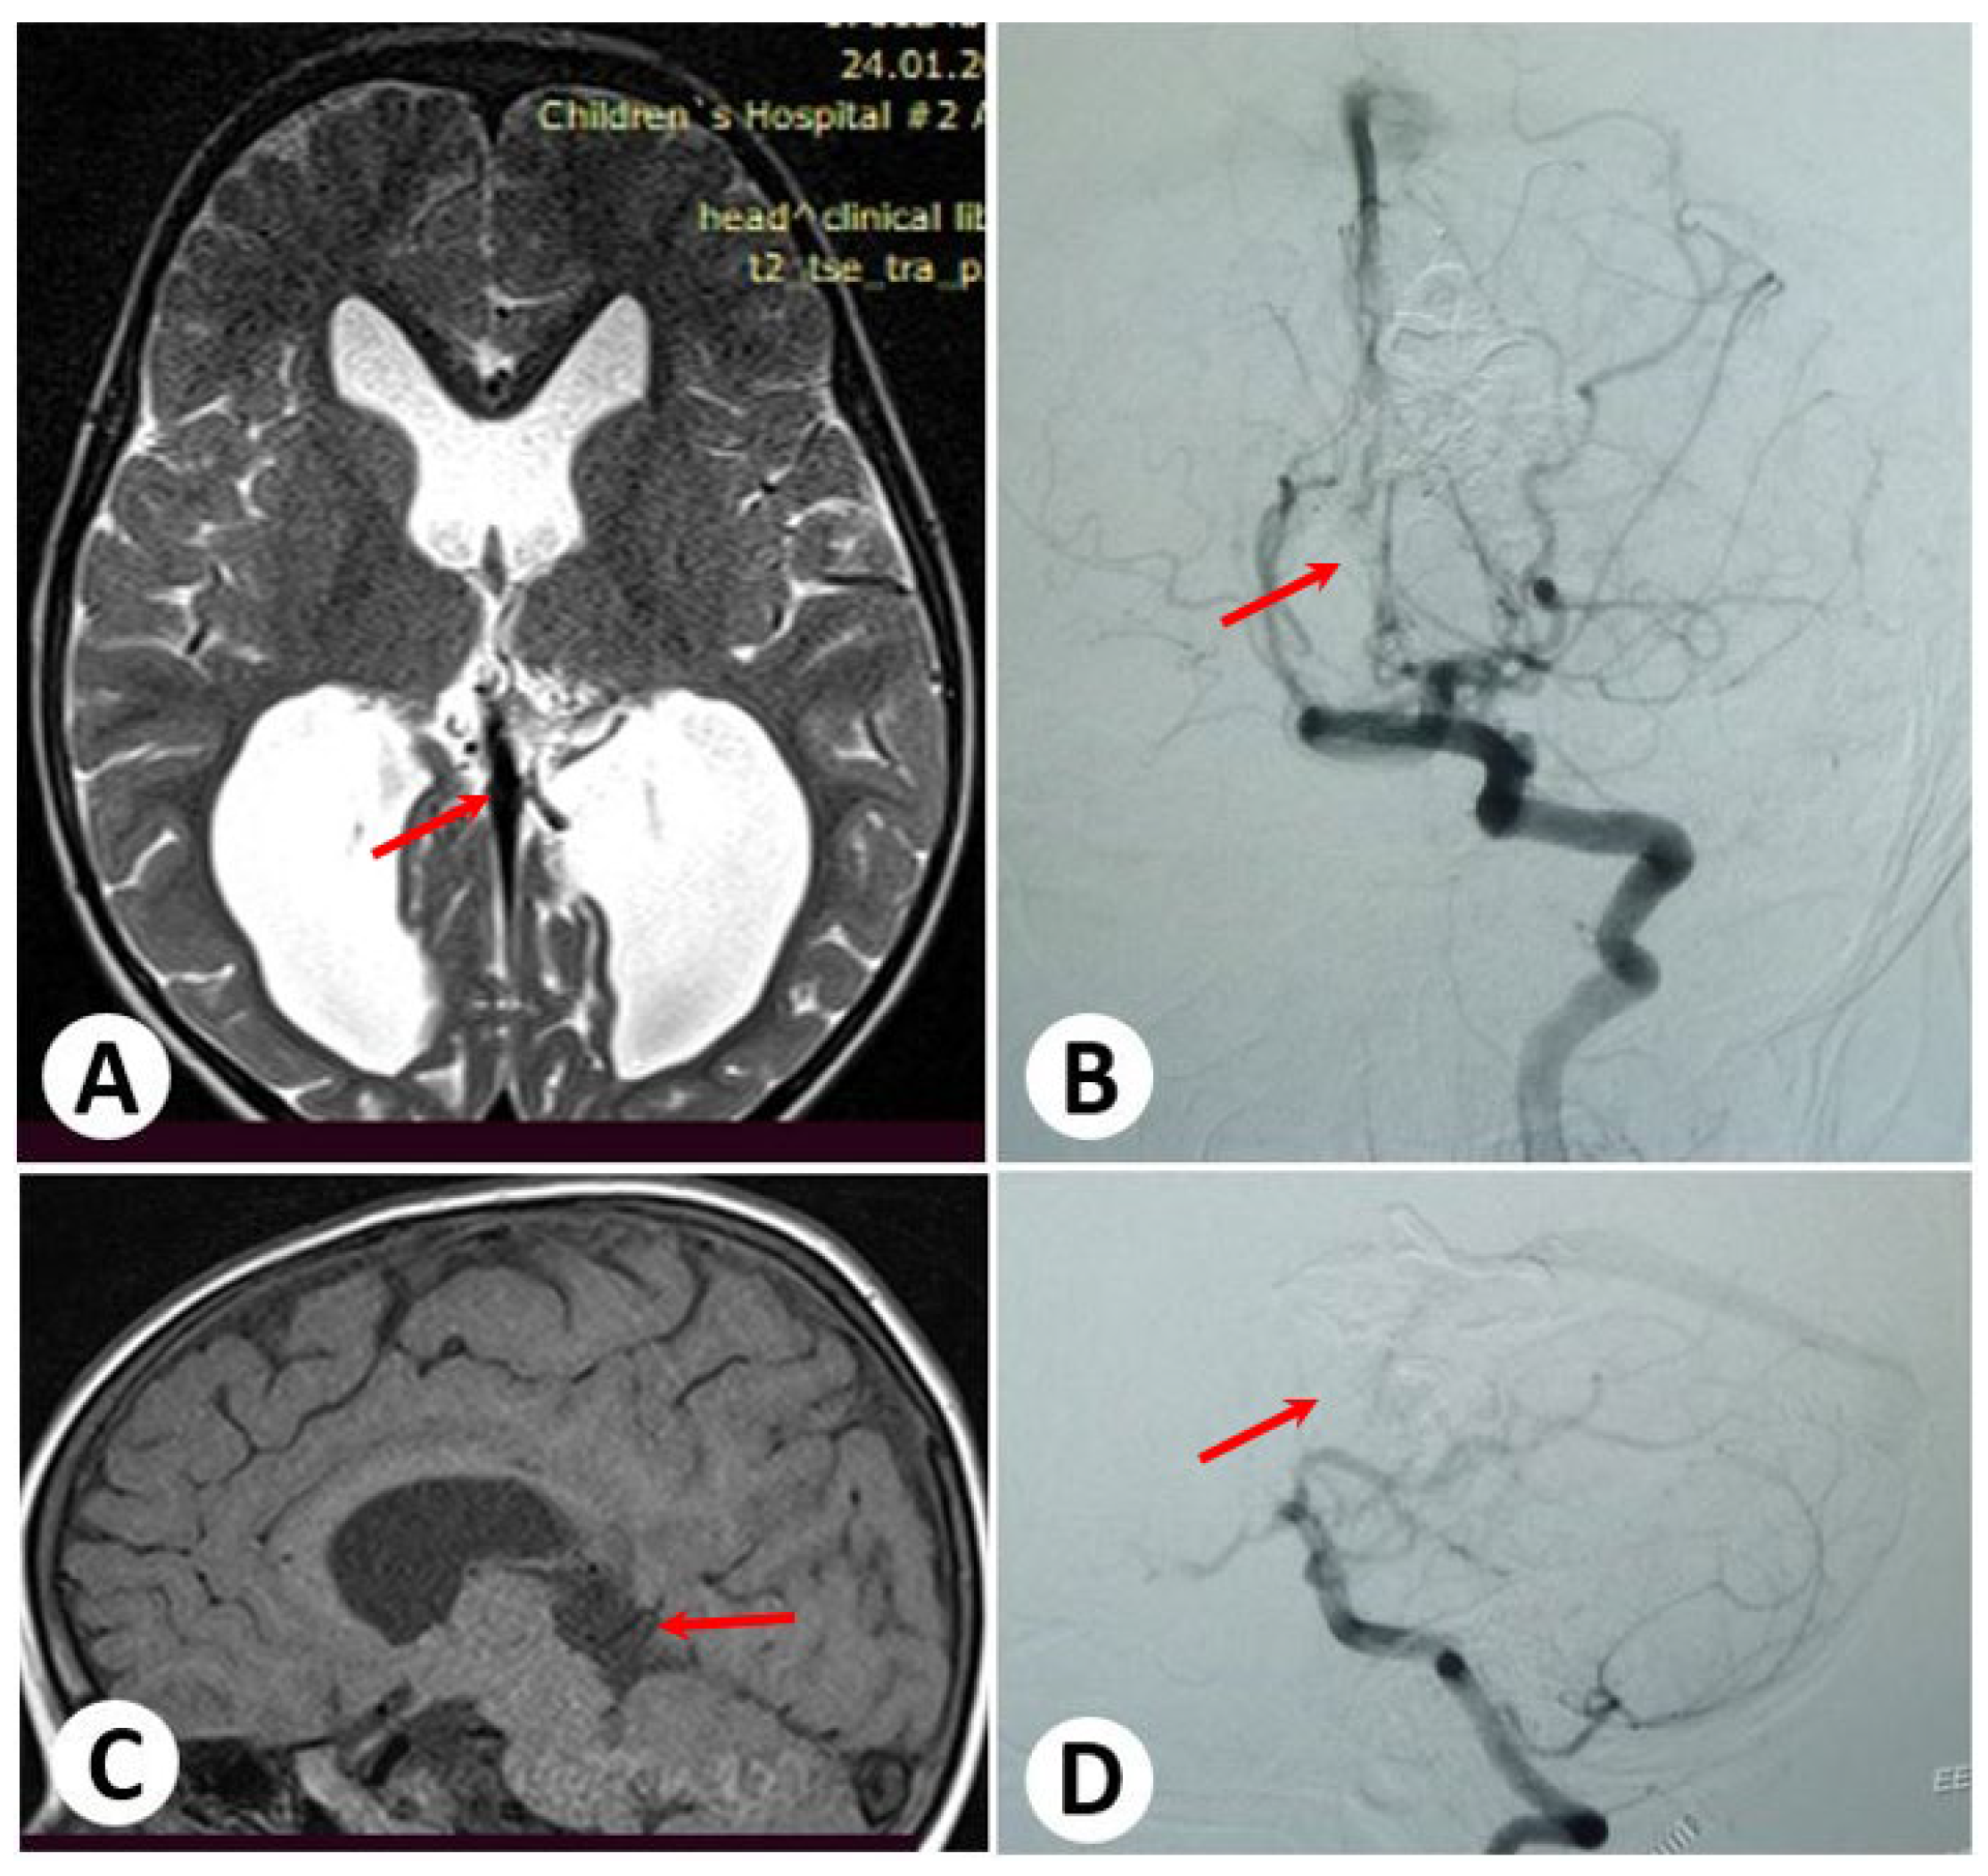

3.1. Illustrative Cases: Case 1